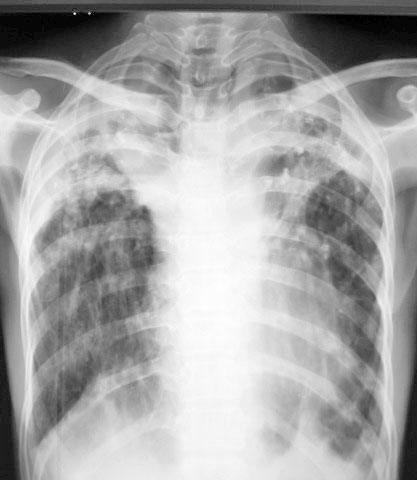

女.45.结核近10年.以结核性腹膜炎入院

双肺上叶可见云絮状密度增高影,密度不均,边缘不清。其中可见类圆形低密度影。右下肺纹理呈垂柳状,膈肌呈幕状,左侧肋膈角消失。支持双肺继发性结核

双肺上叶可见云絮状密度增高影,密度不均,边缘不清。其中可见类圆形低密度影。右下肺纹理呈垂柳状,膈肌呈幕状,左侧肋膈角消失。支持双肺继发性结核,空洞形成